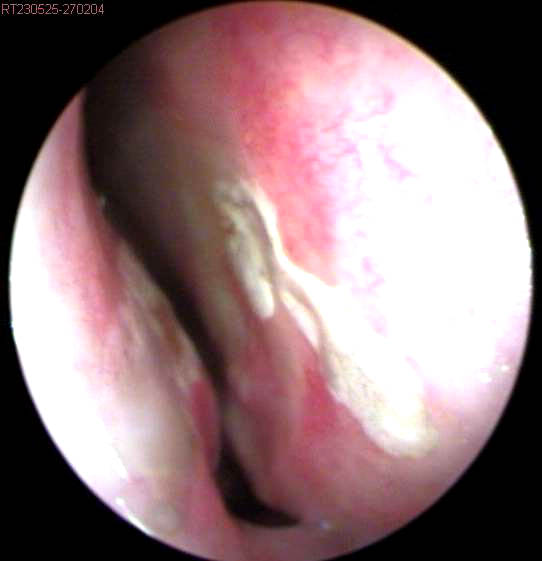

JFC Poliposis nasal bilateral.